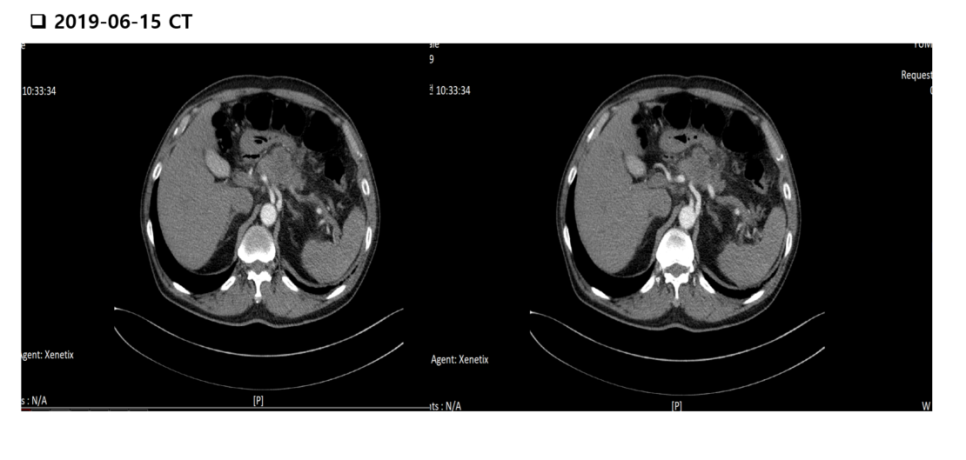

췌장암이 간으로 전이된 72세 박○○씨.

암세포가 상장간막정맥을 침범하였고 최소 37U/ml이하가 정상인 췌장암표지자(CA19-9)가 수치가 20000U/ml 을 넘었고, 5ng/ml이하가 정상인 CEA 수치가 19.6ng/ml나왔습니다. 그것보다 더 힘든 건 항암치료 인해 스스로 걷지도 못하는 상황입니다.

이 환자분은 췌장암으로 종양 크기가 4.3cm인데 문제는 암세포가 상장간맥정맥을 침범하였고, 간에 전이된 상황으로 진단을 받았습니다.

2019년 6월 25일 CEA는 19.6이었고 CA19-9은 20,000이 넘은 상황으로 내원하셨습니다.

이 환자분은 2019년 7월부터 고용량의 셀레나제 주사제(3000mcg/day)와 이뮤코텔 주사를 격일로 투여 받고 셀레나제 경구용제를 날마다 1000mcg/day씩 복용하셨습니다.